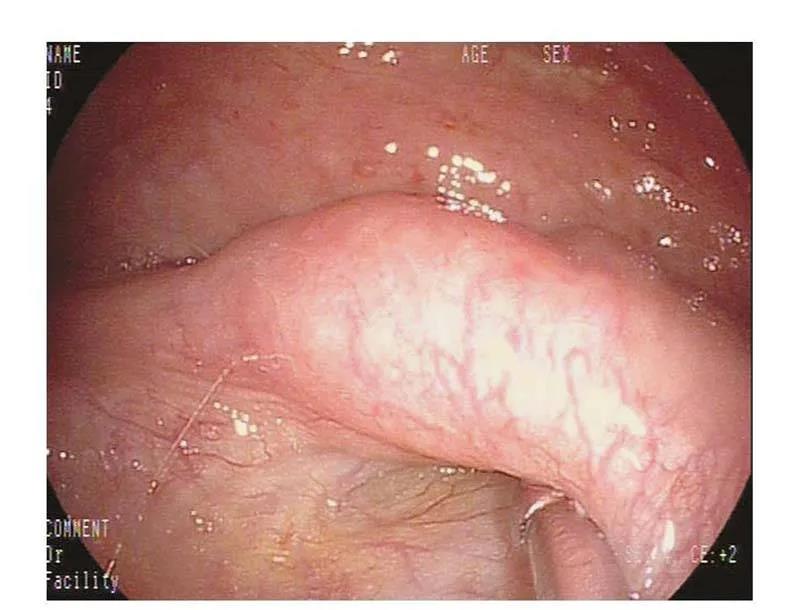

经鼻腔将咽鼓管导管置于咽鼓管咽口(图43-2),用橡皮球向咽鼓管鼓气,听诊器连接橄榄头置于外耳道口、听诊气流通过咽鼓管进入中耳腔及鼓膜的振动声,据此判断咽鼓管是通畅、狭窄或阻塞。传统的导入咽鼓管导管方法有圆枕法和鼻中隔法,近年有学者采用鼻内镜下导入的方法。

经鼻腔将咽鼓管导管置于咽鼓管咽口